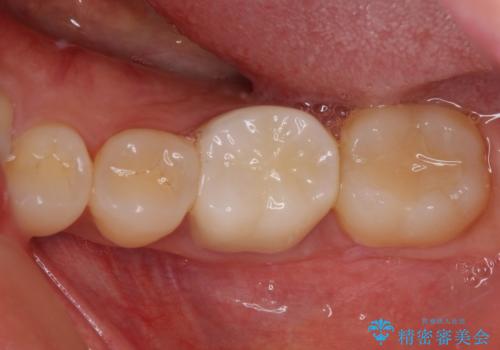

奥歯が痛い。精密根管治療〜オールセラミッククラウン

奥歯の根管治療~オールセラミッククラウン